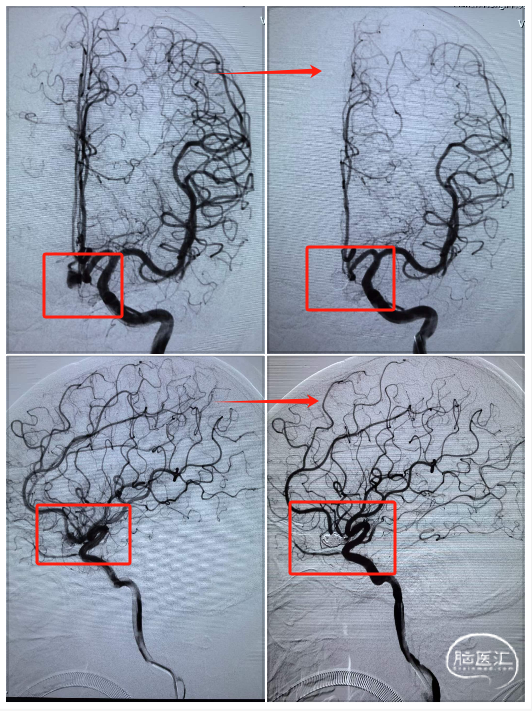

动脉瘤致密栓塞,载瘤动脉血流通畅。

术前术后对比